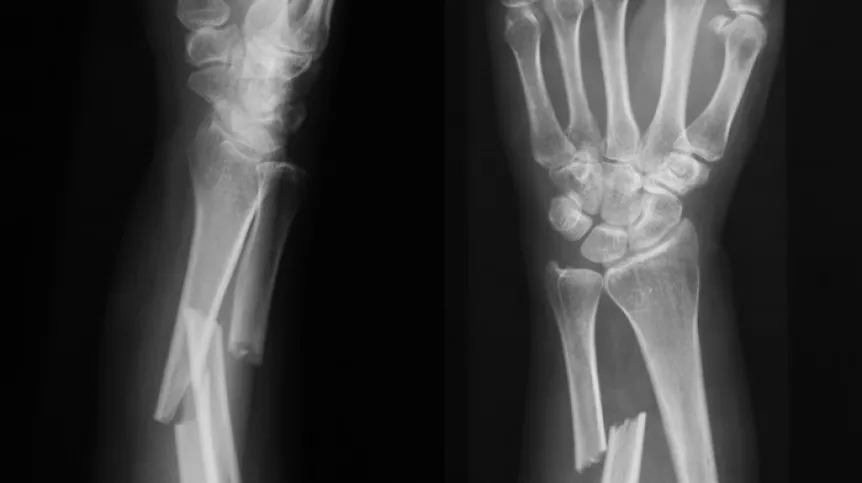

Materiał ma spełniać potrzeby osób, których kości goją się zbyt wolno lub w ogóle się nie zrastają. Problemy z opóźnionym zrastaniem się kości dotykają 5-10 proc. osób z urazami, zwłaszcza przy złamaniach kości udowej i piszczelowej w wyniku wypadków np. samochodowych. Wiek pacjenta wiąże się z ryzykiem - im starszy pacjent, tym większe ryzyko powikłań przy leczeniu złamań, zwłaszcza u osób z osteoporozą. Wśród młodszych pacjentów złamania kości najczęściej wynikają z urazów takich jak kontuzje sportowe, upadki z wysokości, oraz coraz bardziej problematyczne dla systemów opieki zdrowotnej na całym świecie – wypadki komunikacyjne.

Jak podkreśla lider, obecne metody leczenia złamań są kosztowne i czasochłonne. W najtrudniejszych przypadkach przy opóźnionym zrastaniu się stosuje się m.in. przeszczepy kości, wszczepienia rusztowań, a także wstrzykuje się substancje stymulujące wzrost tkanki kostnej. Te procedury często wymagają operacji chirurgicznej, co niesie ze sobą ryzyko powikłań, takich jak krwawienie czy zakażenie.